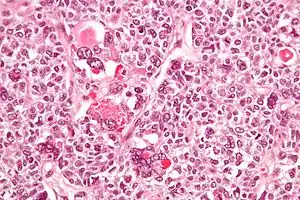

| Micrograph of a juvenile granulosa cell tumour with hyaline globules. H&E stain. | |